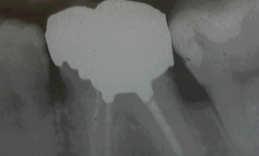

X-ray before treatment